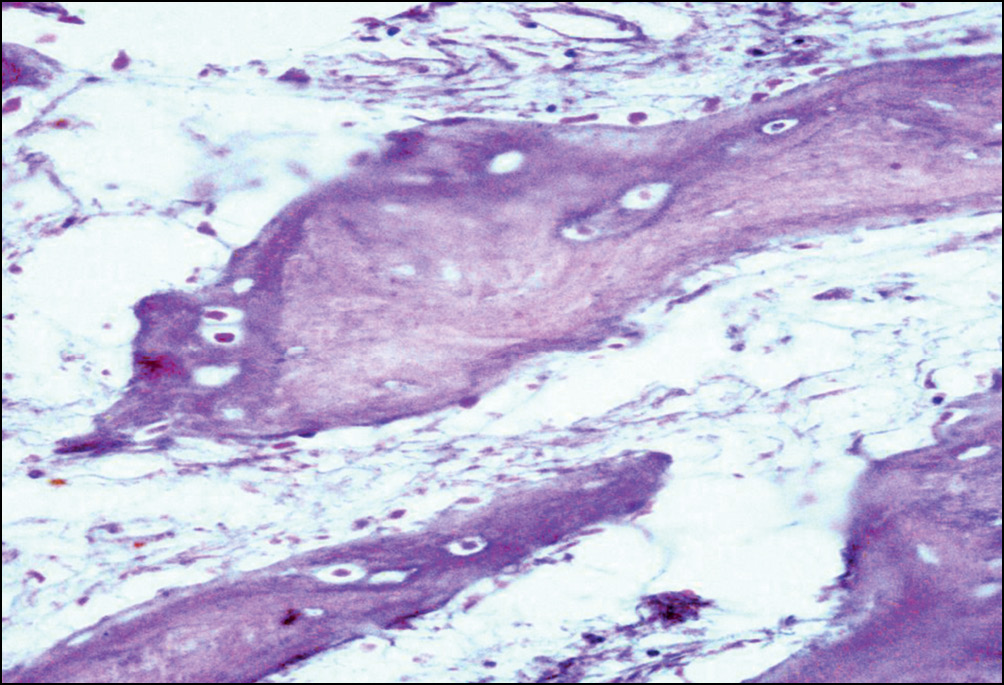

На границе с провизорной мозолью, вдоль формирующихся костных трабекул, обнаруживали очаги гиперплазированных остеобластов, одного из источников остеогенеза (рис. 5).

Рис. 5. Репаративные изменения костной ткани в зоне перипротезных переломов бедренной кости: гиперплазия остеобластов, расположенных вдоль формирующихся костных трабекул. Окраска гематоксилином и эозином. Увел. ×200

Fig. 5. Reparative changes in periprosthetic fractures bone tissue of the femoral component: hyperplasia of osteoblasts located along the forming bone trabeculae. Staining with hematoxylin and eosin. Magnification × 200